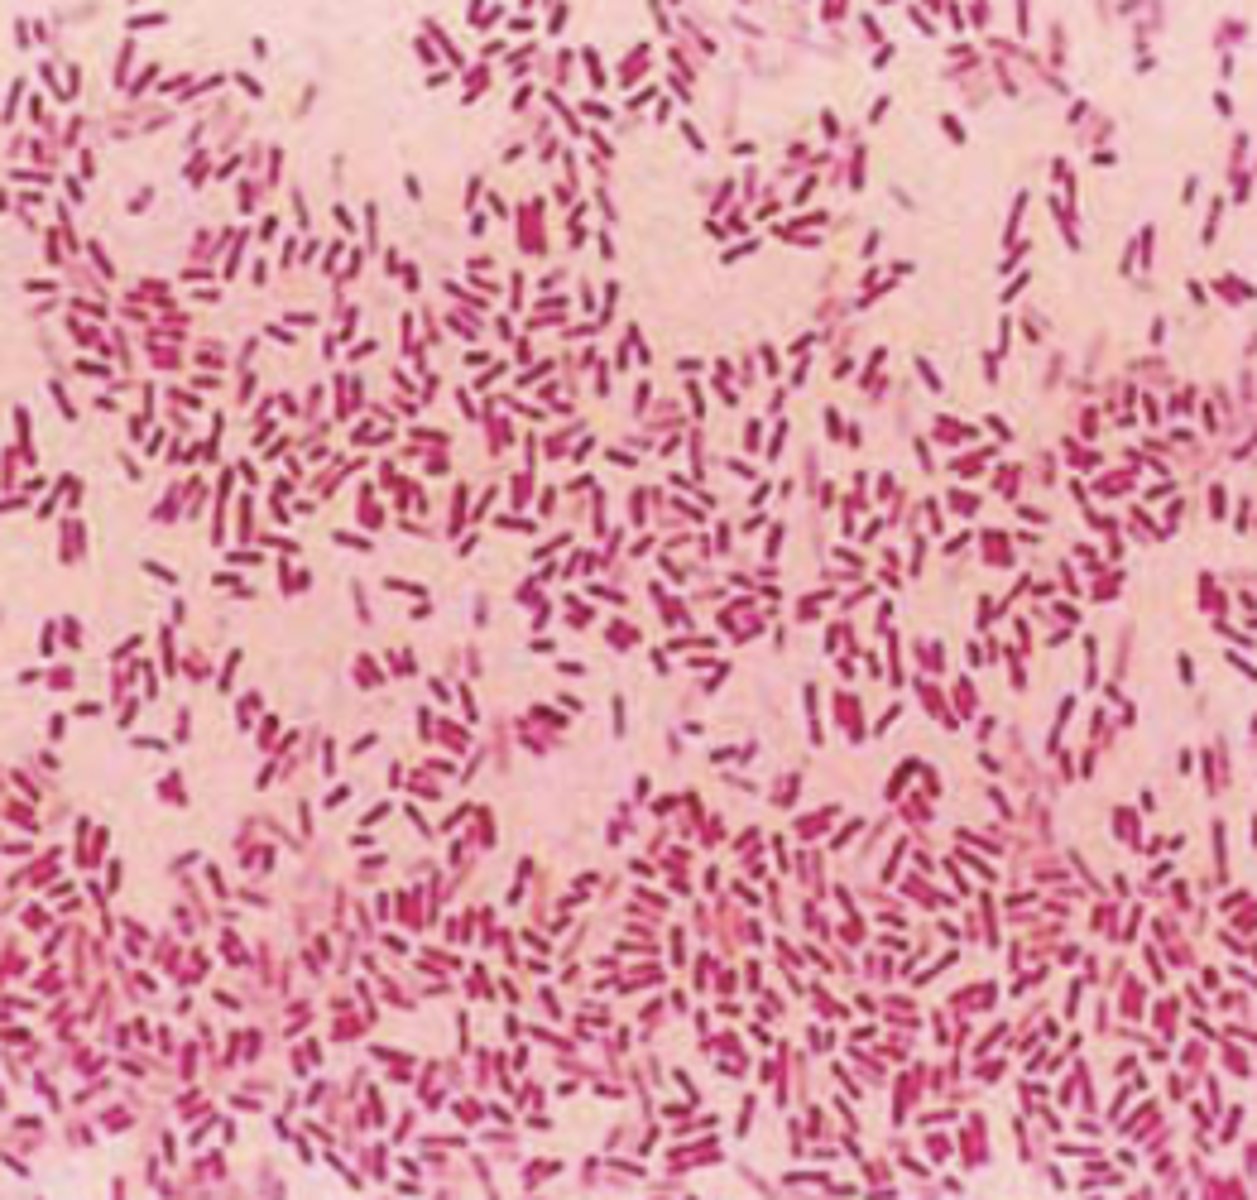

Bacillus (rod-shaped) chains

Identify the bacteria's shape.